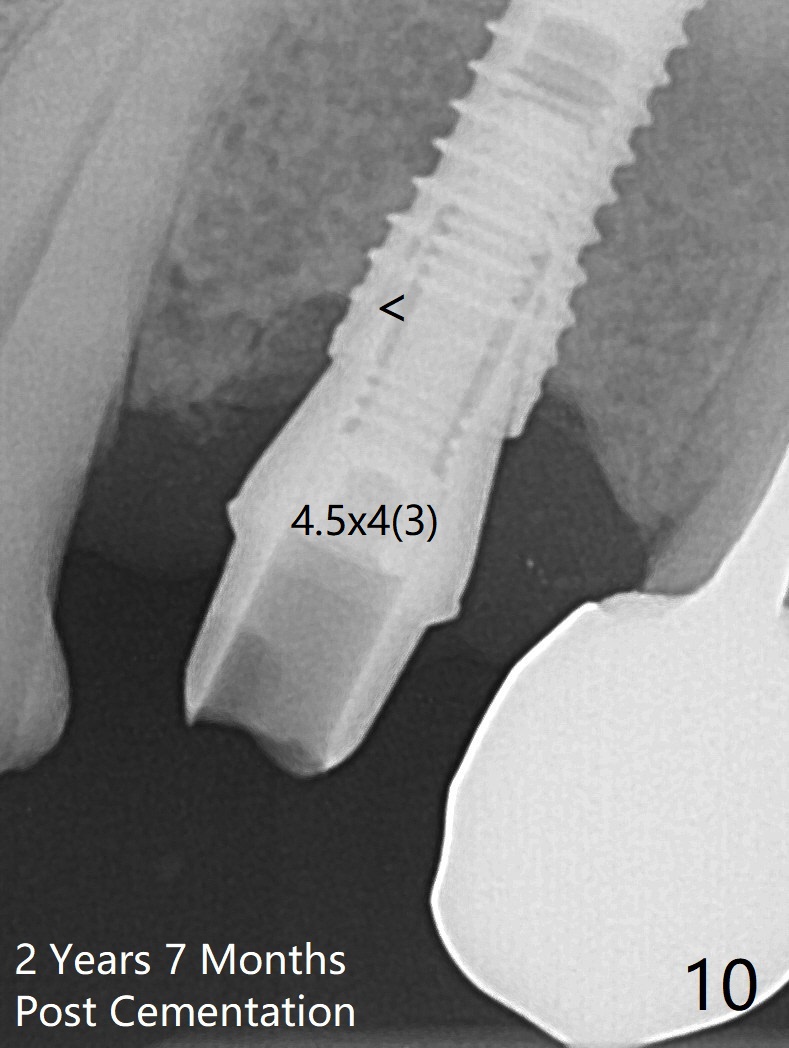

After extraction of the oval-shaped residual roots at #12 (Fig.1), osteotomy is initiated in the palatal socket for 18 mm; since the root of the canine curves distal (Fig.2 red dashed line), the osteotomy cannot afford to move mesial and extend more apical. A 3.8x15 mm implant is placed with > 50 Ncm (Fig.3). With immediate placement of a 4.5x4(3) mm abutment, an immediate provisional is fabricated to close the sockets (Fig.4 P). The provisional has clearance from the RPD clasps (Fig.5). In fact the implant could be longer, as shown by immediately postop panoramic X-ray (Fig.6). The implant seems to be osteointegrated 3 months postop (Fig.7). The tooth #13 is symptomatic with caries (Fig.8 C) 7 months post #12 crown cementation; the #13-15 FPD dislodges. The upper left quadrant is cold and hot sensitive 2.5 months post RCT (Fig.9); although there is mild percussion at #13, pulpal test shows that the tooth #15 has lingering pain. The FPD was recemented temporarily after RCT; it cannot be removed. The implant crown has been loose for several months during the pandemic before he returns 2 years 7 months post cementation. In fact the abutment has been not seated completely (from Fig.3 to 9). The crown/abutment is removed from the mouth; the crown is sectioned and separated from the abutment; the latter is reseated, but incompletely (Fig.10 <). With suspicion of the mesial crestal contact, profile drills 4.6 and 5.5 mm are used without effect. A new (old probably being worn) and longer (easy to turn in the narrow space) abutment is finally seated completely (Fig.11 (no gap)). After occlusal adjustment, abutment level impression is taken for a new crown.